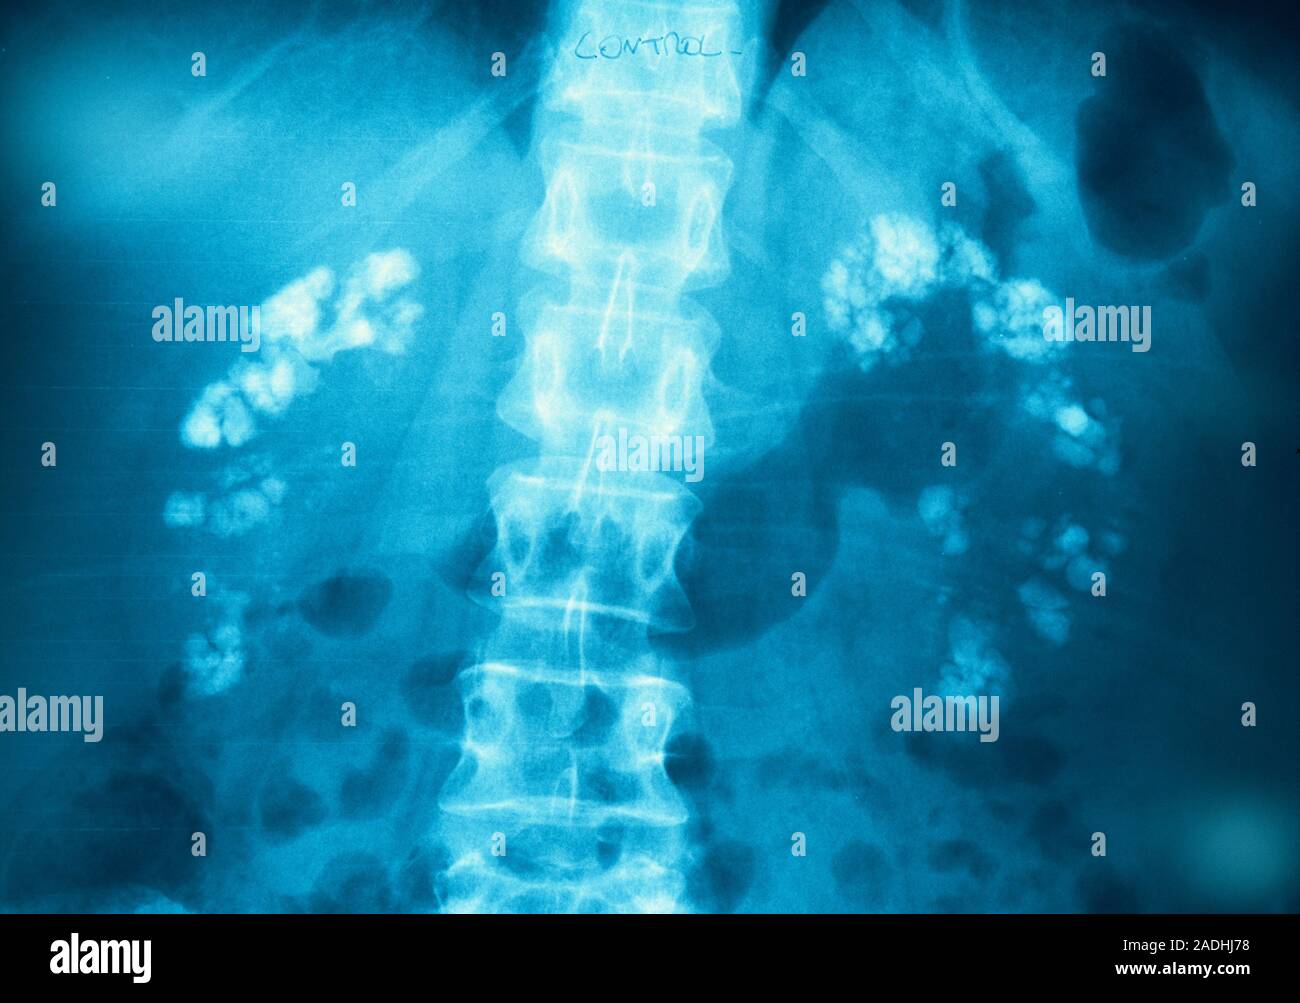

From www.alamy.com

Kidney calcification. Xray of the abdomen of a patient with What Causes Calcium Deposits In Kidneys the clinical presentation and prognosis of nephrocalcinosis. Nephrocalcinosis refers to generalized calcium deposition in the kidney and does not include the focal calcium deposition. People with this may also have high levels of calcium or. calcium phosphate deposition disease is caused by the development of calcium phosphate crystals within the renal tubules and. nephrocalcinosis is a condition. What Causes Calcium Deposits In Kidneys.